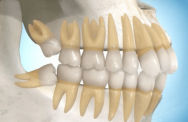

Possíveis posicionamentos de 3º molares

O último dente a se desenvolver e erupcionar na boca é o 3º molar. Normalmente erupcionam aos 18 anos. Geralmente os 3º molares não tem espaço para erupcionar sendo indicada sua extração, sejam por fins ortodônticos ou profiláticos, para evitar problemas futuros como a reabsorção dos 2º molares, cistos e tumores, entre outros. Estes dentes podem erupcionar parcialmente dificultando a limpeza, acumulando alimentos, placas e bactérias na gengiva sobreposta o que pode resultar em cáries, doenças gengivais, abscessos e infecções não só nos 3º molares como nos dentes vizinhos. Os sisos podem ser extremamente problemáticos, sendo necessária a intervenção de um especialista Buco-Maxilo para sua remoção.